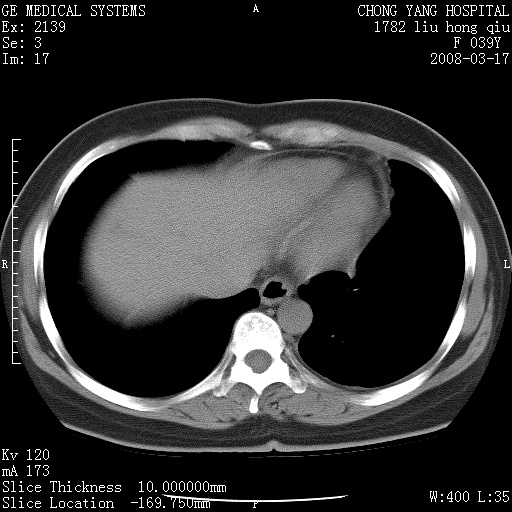

以下是引用yangxue121在2008-5-31 20:24:00的发言:[br]考虑多发胸膜间皮瘤[br]左侧少量胸腔积液[br]肝脏密度不均

以下是引用长城干红在2008-5-31 21:42:00的发言:[br]肝脏密度不均,建议增强扫描,胸膜下多发结节,考虑为胸膜来源的原发肿瘤或转移瘤。